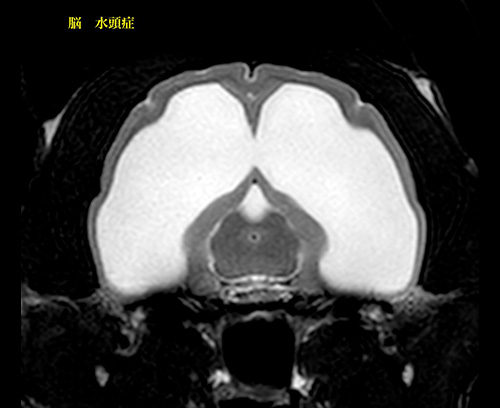

水頭症